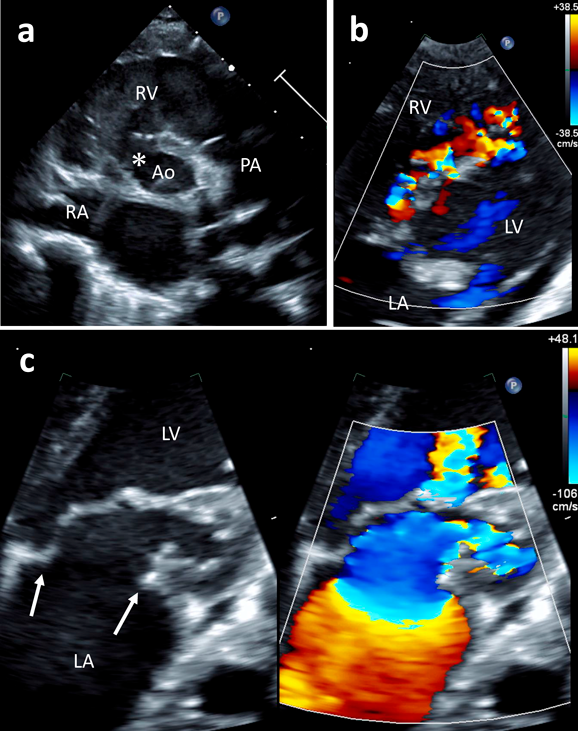

心臓超音波検査(Fig. 1,Movie)

Fig. 1 Echocardiogram shows multiple VSDs and supra-mitral ring

(a) Parasternal short axis view shows perimembranous VSD(asterisk). (b) Four chamber view shows multiple muscular VSDs. (c) Four chamber view of the supra-mitral ring (intra-mitral variant). Ao, aorta; LA, left atrium; LV, left ventricle; PA, pulmonary artery; RA, right atrium; RV, right ventricle; VSD, ventricular septal defect